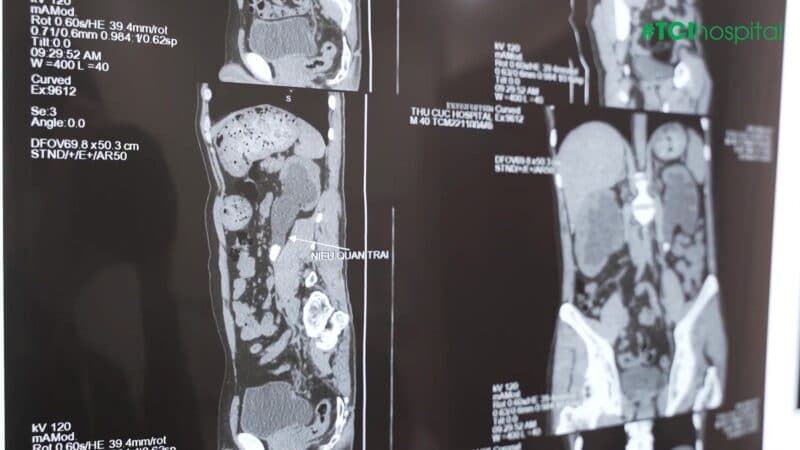

Dù bệnh nhân cảm nhận rõ cơn đau vùng hông lưng bên phải, nhưng tổn thương nghiêm trọng hơn lại nằm ở bên thận trái, nơi gần như không có biểu hiện triệu chứng rõ rệt. Hình ảnh chẩn đoán ghi nhận sỏi niệu quản 1/3 trên kích thước khoảng 20x11mm và sỏi đài thận dưới 9x6mm gây giãn đài bể thận độ IV – Mức độ nghiêm trọng nhất với tình trạng mỏng nhu mô rõ rệt. Trong khi đó, thận phải xuất hiện sỏi vị trí nối bể thận – niệu quản kích thước đến 25x18mm, gây giãn đài bể thận độ III.

Hình ảnh sỏi niệu quản trái gây giãn đài bể thận độ IV